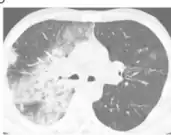

Diagnosis

The diagnosis of bacterial pneumonia is based on the following:[5]

- Chest X-ray